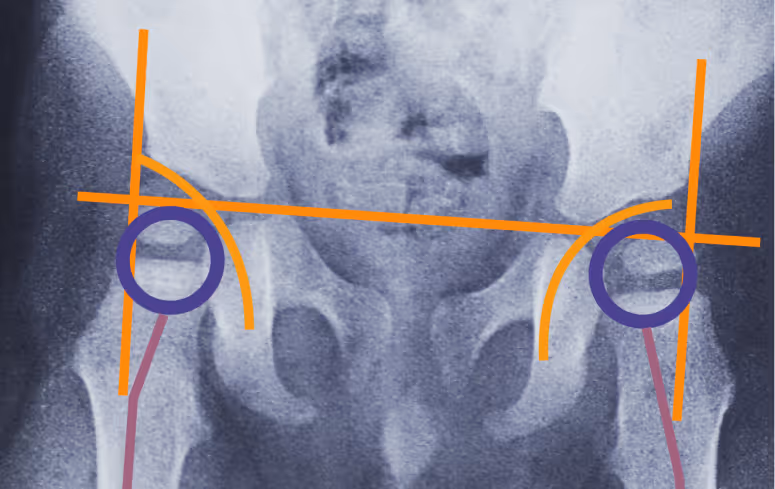

Диагноз ставит врач на плановом осмотре. Не все изменения в тазобедренных суставах можно увидеть на УЗИ, поэтому пациентам со СМА рекомендуется делать рентгенографию — по снимку врач определяет состояние суставов и решает, какие меры принимать.

Небольшое смещение головки бедренной кости, подвывих, полный вывих — все эти изменения ещё называют дисплазией тазобедренного сустава.

Нестабильность тазобедренных суставов может привести к вывиху бедра. В такой ситуации нога примет вынужденное положение, может болеть — а это значит, что ребёнку будет сложно стоять, сидеть, и в целом качество жизни ухудшится.

Да, но тут важны нюансы. Действительно, при подвывихах бедренных костей без других сопутствующих заболеваний ребенка не рекомендуется вертикализировать, чтобы не спровоцировать вывих. Однако для пациентов со СМА позный режим и вертикализация в том числе — важнее. Если есть угроза вывиха, вертикализацию проводят с отведением бедер — так и улучшается положение головок бедренных костей, и создается правильная нагрузка на сустав, способствующая его стабильности [2]. Степень отведения и другие настройки системы для стояния определяет специалист.